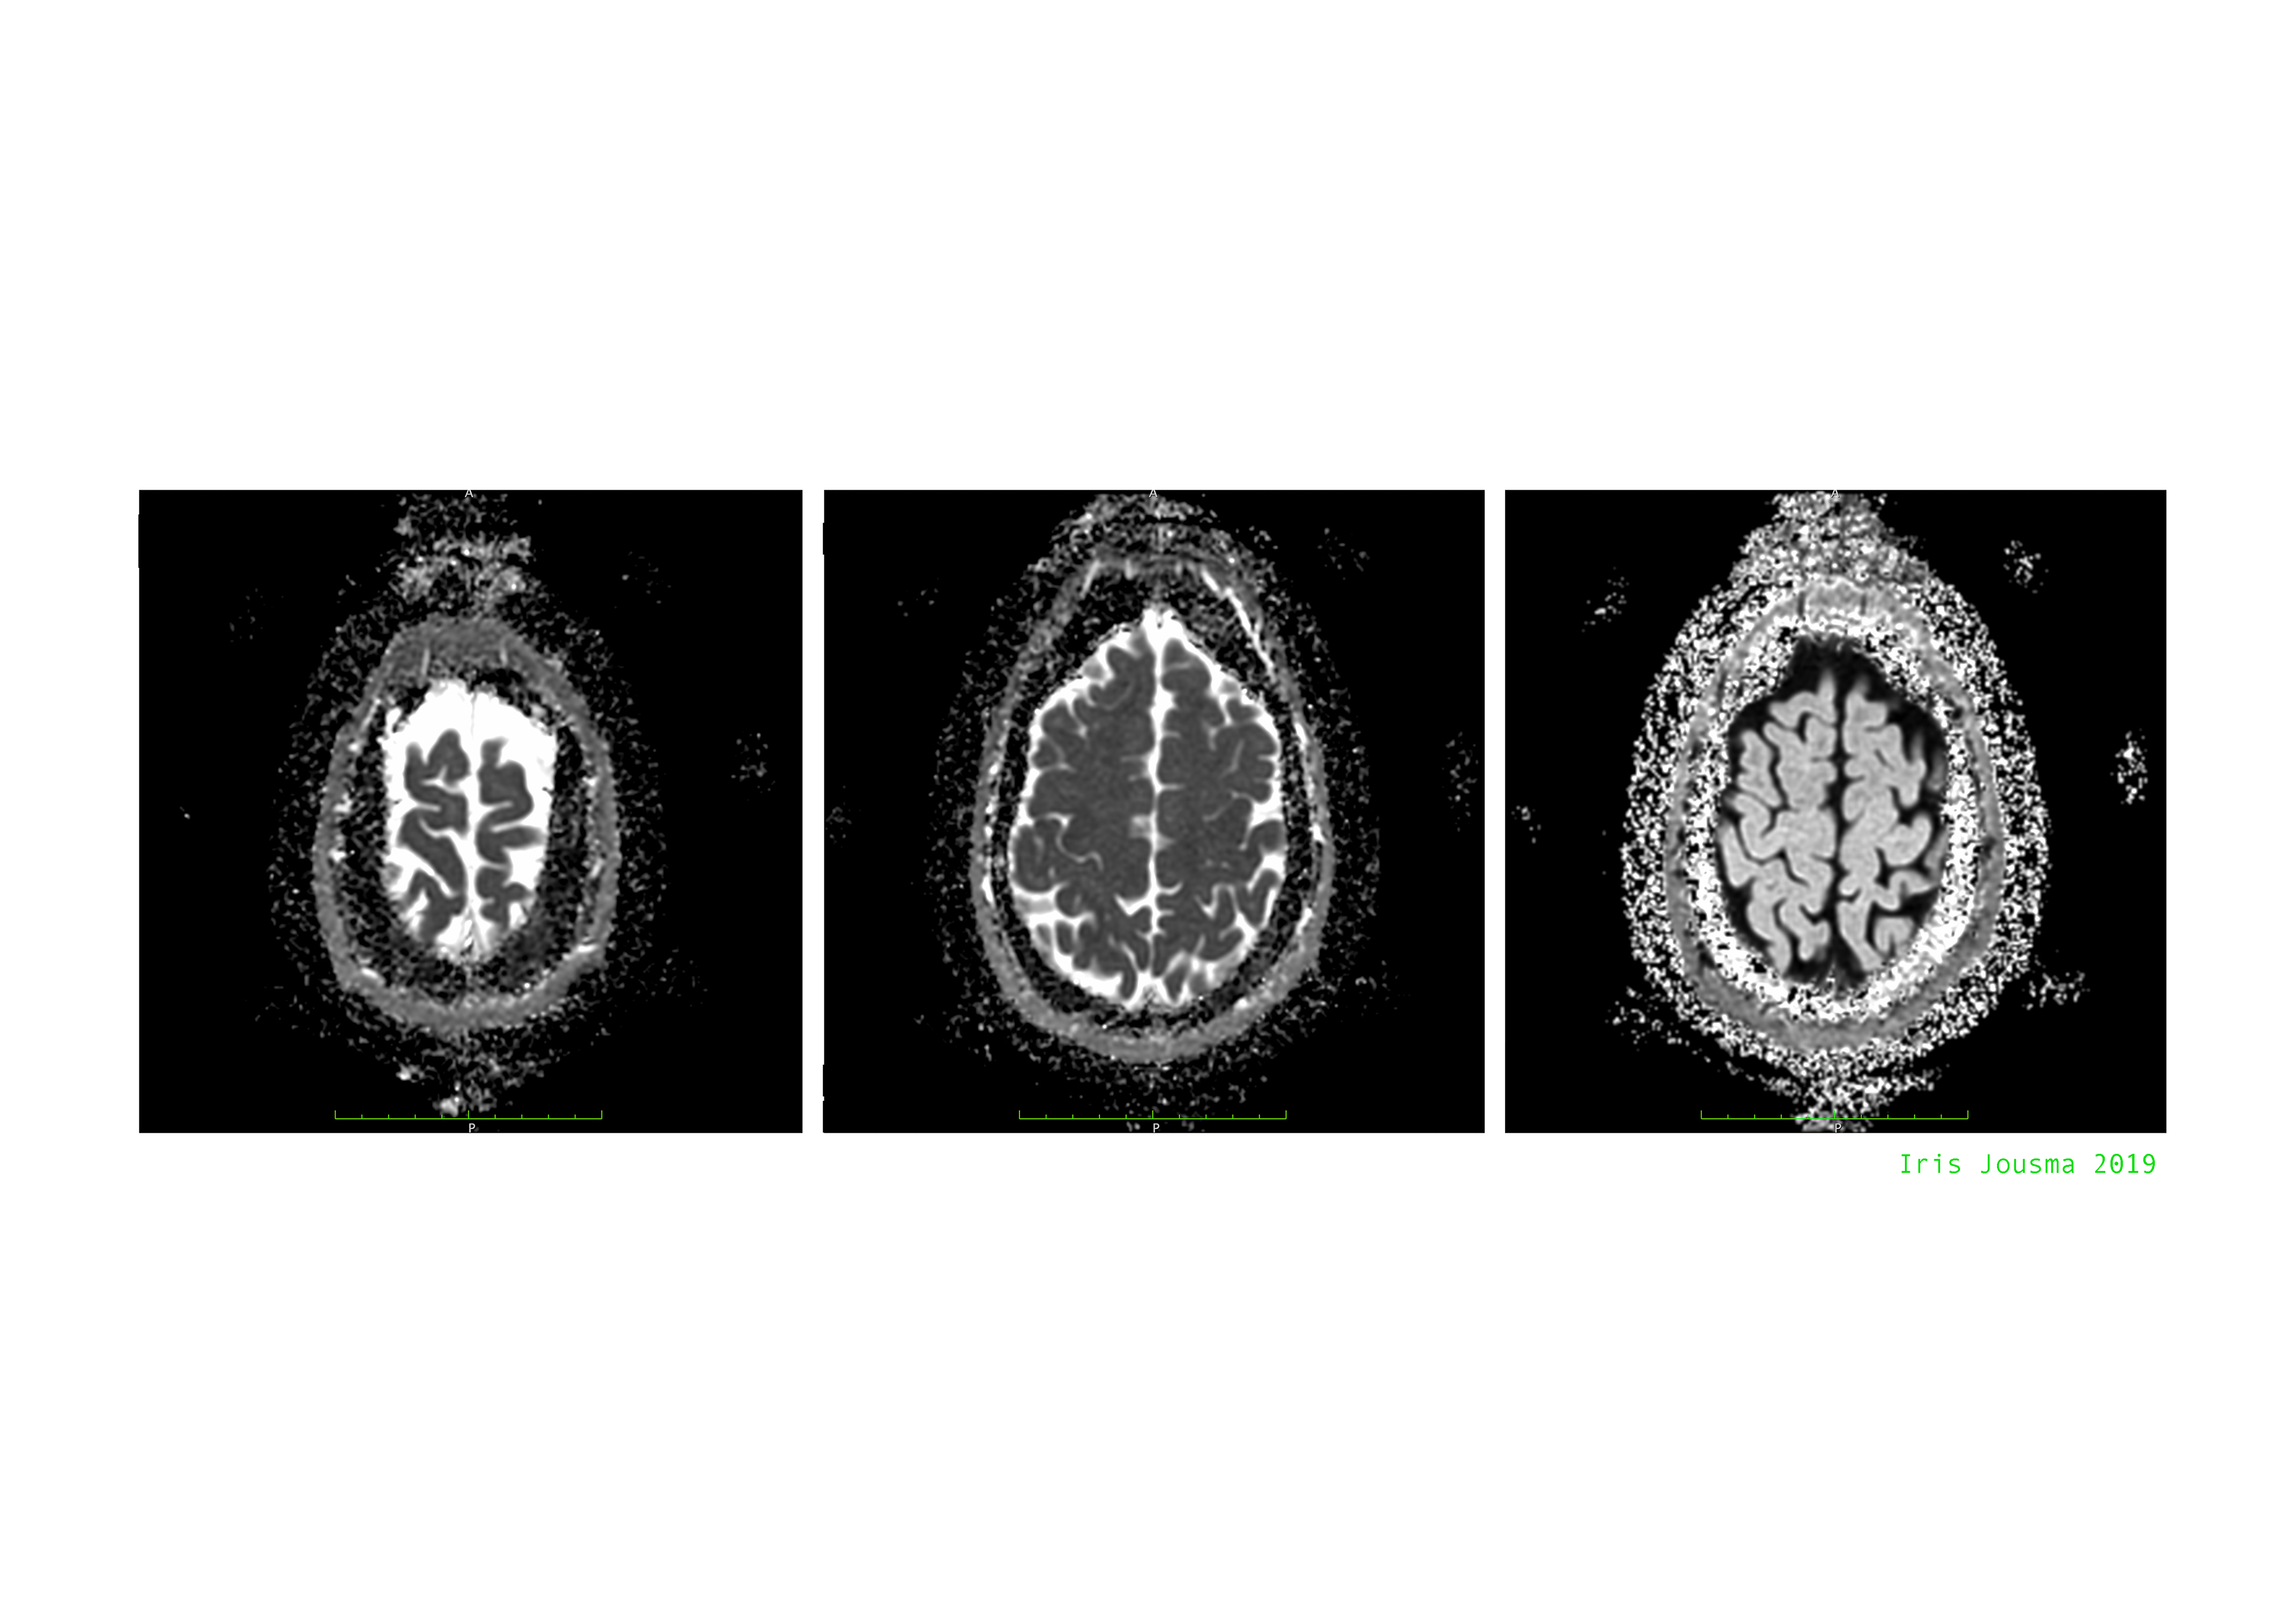

Foto's door Annette van der Goes, Amsterdam MS Centrum

Van Links naar rechts: Martha Lameris, Iris Jousma, Andrea van Sloterdijck en Lisette Oliemeulen 2019